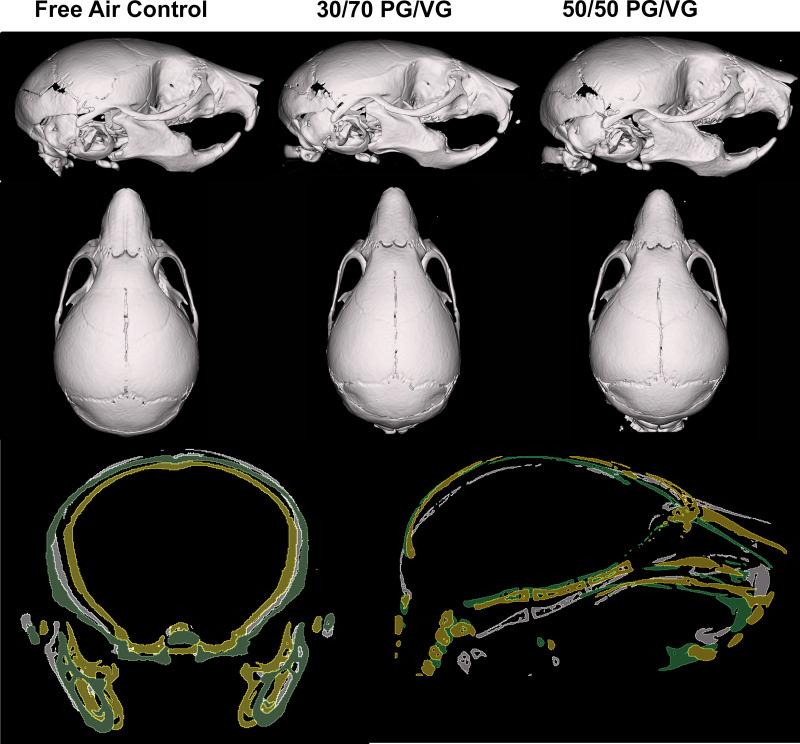

In utero exposure to electronic cigarette carriers alters craniofacial morphology.

Adult breeder mice were utilized to generate in utero ENDS component exposed litters including free air exposure (control), 30/70 PG/VG, and 50/50 PG/VG groups. The resulting pups were assessed at postnatal day 14 for skull morphology.

Data demonstrate significant reductions in body weight, facial, and cranial dimensions, where there was a significant reduction in growth for the 30/70 PG/VG exposed group. There were no significant differences found between control and 50/50 PG/VG.